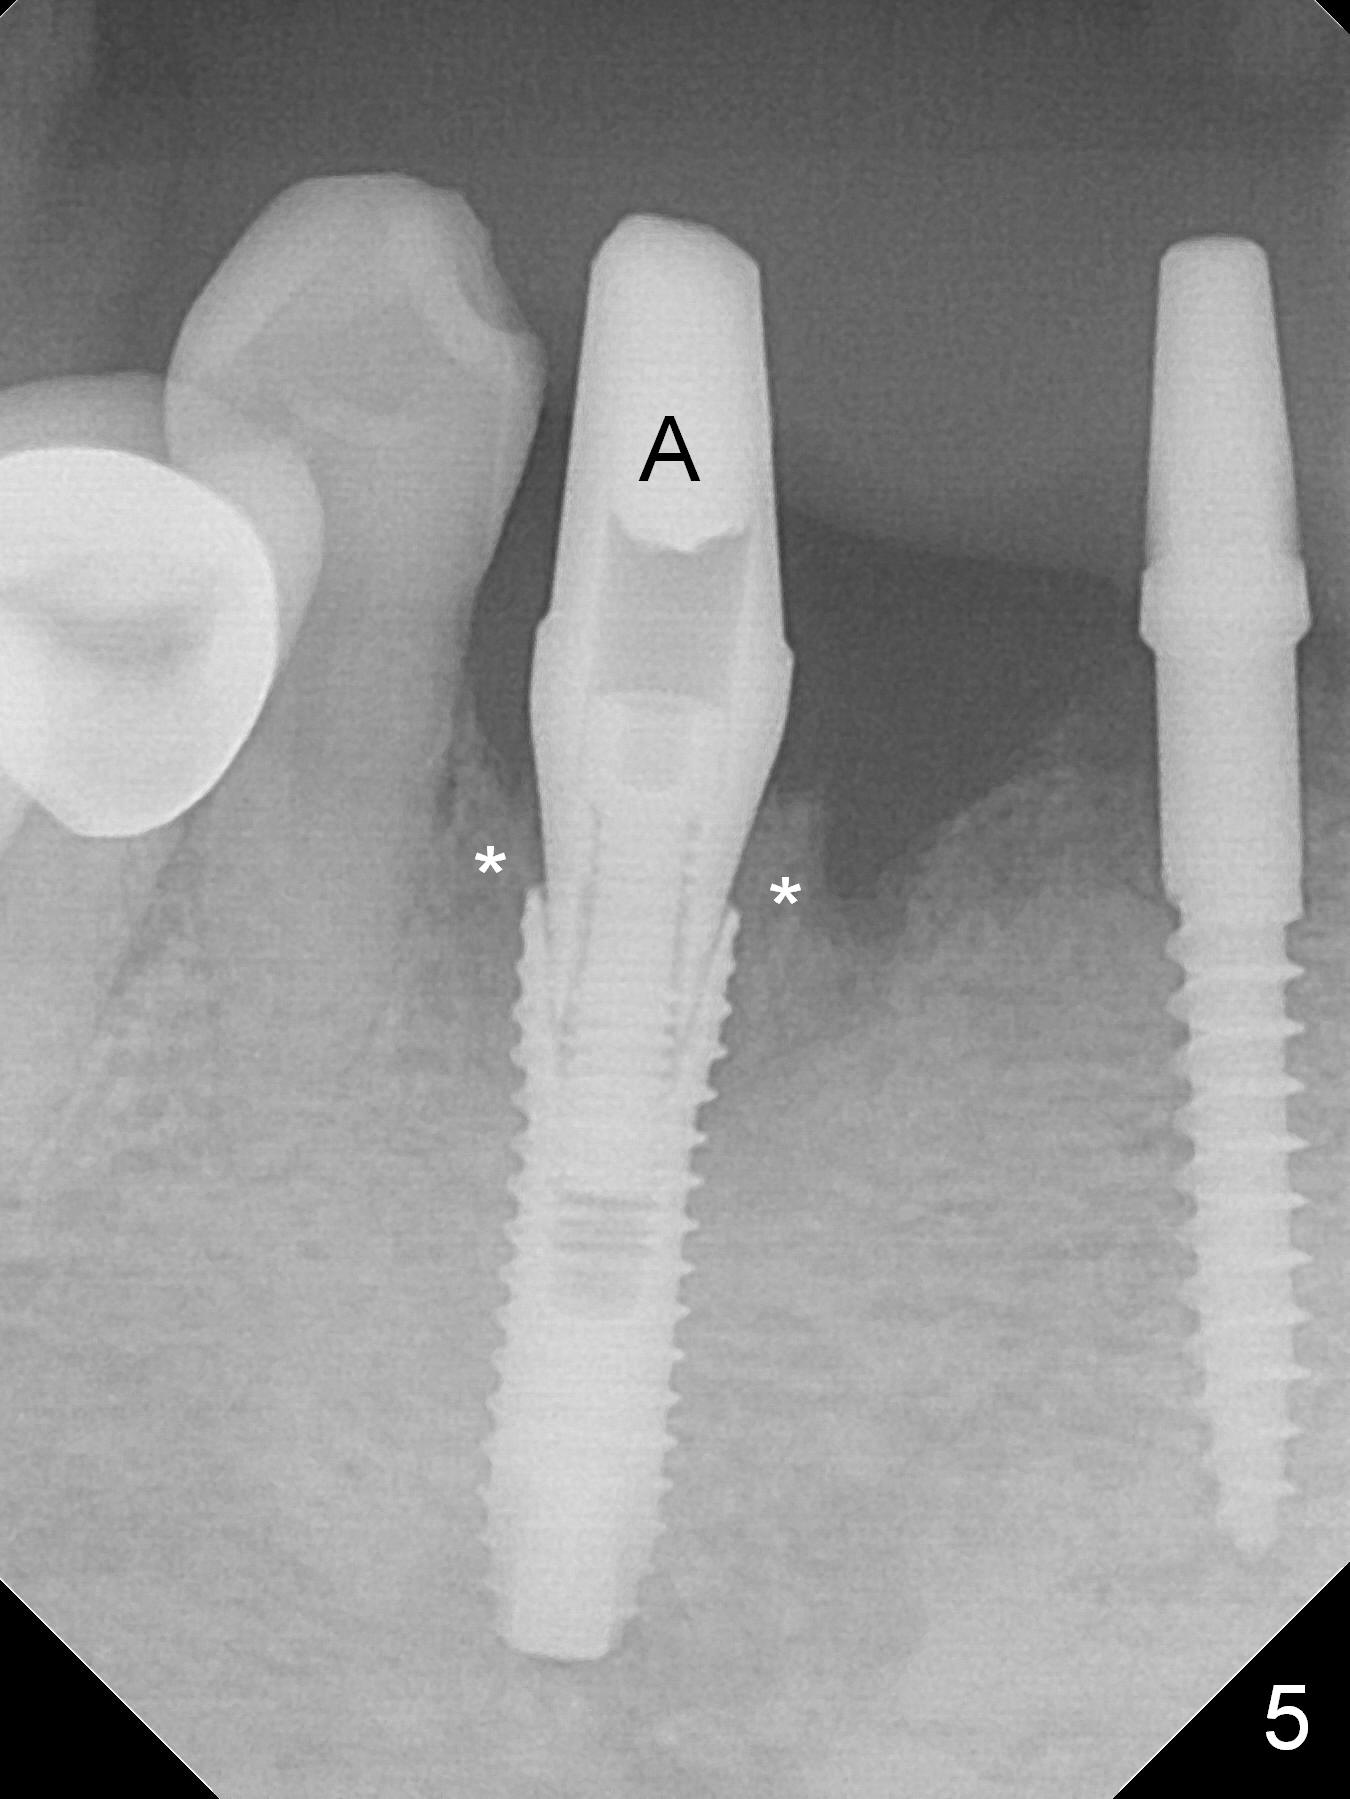

There is severe buccal gingival recession at #27 (Fig.1 arrow), as compared to that at #22. After removing the bridge and extraction of #27 (Fig.2 with severe loss of the buccal plate), a 3x18 mm drill is used to finish osteotomy (Fig.3). A 3.8x13 mm UF implant (Fig.3 green line) will be placed with 9 mm in the apparently solid, native (new) bone (blue line), while the coronal 5 mm will be occupied by the 5 mm cuff of a cemented abutment (pink line). The white dashed line is the gingival margin. The osteotomy is initiated as lingual as possible so that there will be at least 2 mm buccal gap when the narrow implant is placed. In spite of effort and precaution (guided surgery could control the trajetory), the coronal end of the implant tilts buccally so that a 4.5 mm 15 ° A 4 mm angled abutment is placed slightly subgingival (except buccal; Fig.5 A).

The mesial defect at #27 appears to have been repaired 8 months postop (Fig.8,9 *); there is no bone loss at 1-piece implant sites. The gingival recession seems to remain the same before and after removal of the provisional FPD (Fig.10,11). The bulging abutment at the cervix is less prominent when a straight abutment is used and prepared (Fig.12, 4.5x5.5(5) mm). There is no bone loss at #23, 25 and 27 sites 2.5 years post cementation (Fig.12-15), although the trajectory of the implants could be improved by using surgical guide (Fig.16-18).